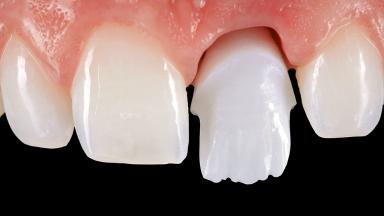

Surgical Management of Peri-Implantitis: Open-Flap Debridement with Seven-Year Follow-up After Treatment

This case describes both a surgical and an anti-infective approach for the management of peri-implantitis, including treatment of the entire dentition to eliminate any deep periodontal pockets that could serve as reservoirs for bacterial re-colonization at the implant site. A 65-year-old female patient was referred to the periodontist in 2013 for assessment and management of an infection at implant 12. On examination, probing depths at implant 12 were 11 mm with suppuration and bleeding on probing.